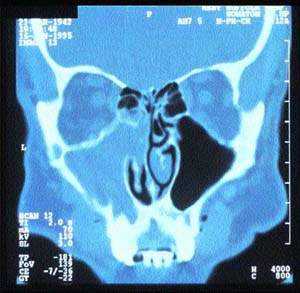

Наиболее специфичным методом оценки анатомии и патологии пазух носа является компьютерная томография, как правило, в проекции венечного шва (рис. 4).

Компьютерное сканирование пазух дает точную информацию об анатомии пациента и наличии патологических изменений (рис. 5). Однако это исследование следует проводить только после специализированного обследования, включающего и назальную эндоскопию.

| Рисунок 4. Компьютерное сканирование синусов |